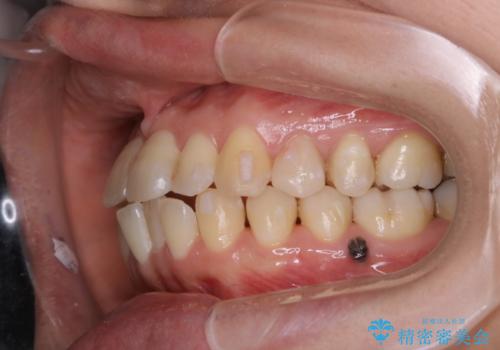

- 右上の2番目の歯が内側に入っているのと、下の前歯のがたつきが気になるとご相談にいらした方です。

上下左右の歯を後ろに動かして歯を並べるスペースを確保し、内側に入っていた歯を綺麗に並べ、前歯の中心もお顔の中心に合うようにしました。

矯正用アンカースクリューを埋入し、上下左右の歯を後ろに動かすことで歯を並べるスペースを作りました。

元々内側に倒れていた右下の奥歯は、ゴムかけを追加で行っていただくことによりしっかり起こすことが出来ました。

歯並びが綺麗になったことでモチベーションが上がり、銀歯からセラミックへのやり替えも行っております。